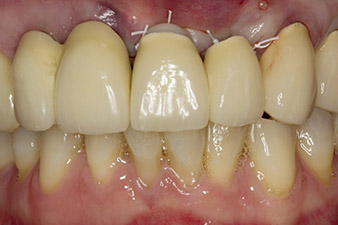

Nach primärer Abheilung werden die Weichgewebe mithilfe der basal unterfütterten Brücke ausgeformt. Zwei Monate später erfolgt die Freilegung mit einem leicht palatinal gelegten Kieferkammschnitt (Abb. 2).

Der Alveolarknochen erweist sich an Position 22 als ausreichend dimensioniert. Die Abbildungen 2 und 4 zeigen die Implantatbett-Aufbereitung, den Gewindeschnitt und die Implantation mit dem Implantmed.